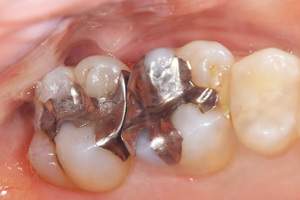

経年劣化していた銀歯の歯

麻布十番歯科で銀歯の中が虫歯になっている症例の口腔内写真